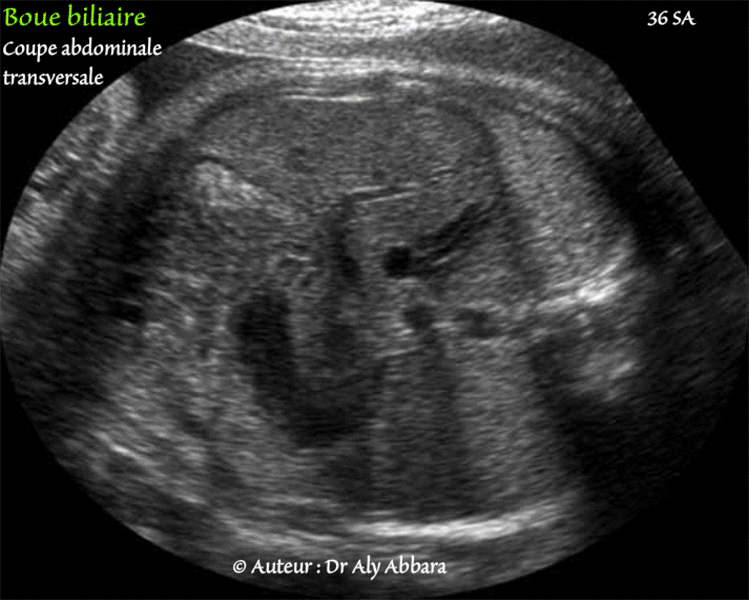

(Fœtus âgé de 36 SA).

• Coupe échographique abdominale transversale centrée sur la partie inférieure du foie et montrant une vésicule biliaire à contenu hyperéchogène traduisant la présence dans sa cavité de la bile concentrée, épaisse connue sous le nom de " boue biliaire ".

On remarque l'absence d'atténuation distale acoustique (ou cône d'ombre) derrière la vésicule biliaire.

• Cet aspect de " boue biliaire " disparaît habituellement dans les premières semaines de vie.